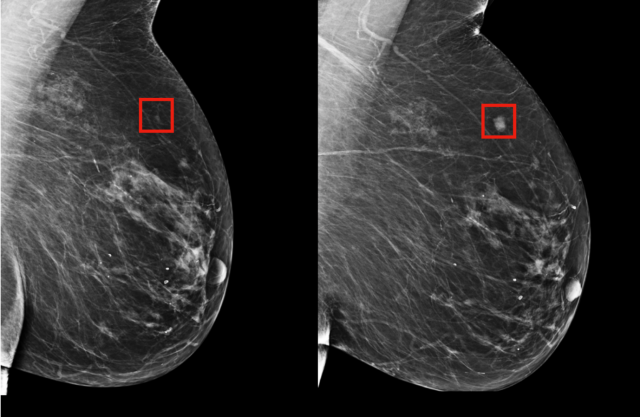

Máme tu i jeden příklad, kdy AI byla schopna odhalit počátek zhoubného bujení (vlevo) celé čtyři roky před tím, než se vytvořil nádor (vpravo). To je samozřejmě pouze příklad a výzkumníci v něm jen využili dostupné snímky, v jejichž případě už sami věděli výsledek, ale umělé inteligenci to samozřejmě "neřekli".